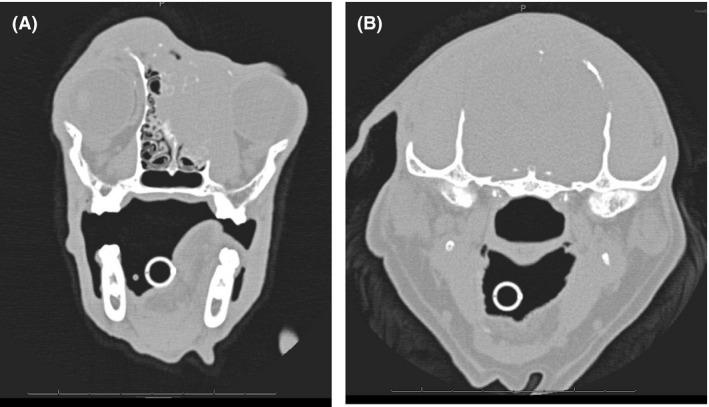

一只患有额窦鳞状细胞癌的犬的眶顶切除术及化疗:病例报告与文献综述

Superior orbitectomy and chemotherapy in a dog with frontal sinus squamous cell carcinoma: a case report and review of the literature.

A superior orbitectomy can be a challenging but accomplishable surgical option in dogs with a tumor which involves the dorsal bony part of the orbit. The procedure described in this report can be vision-sparing and life prolonging even in a case of an aggressive growing frontal sinus squamous cell carcinoma.

摘要